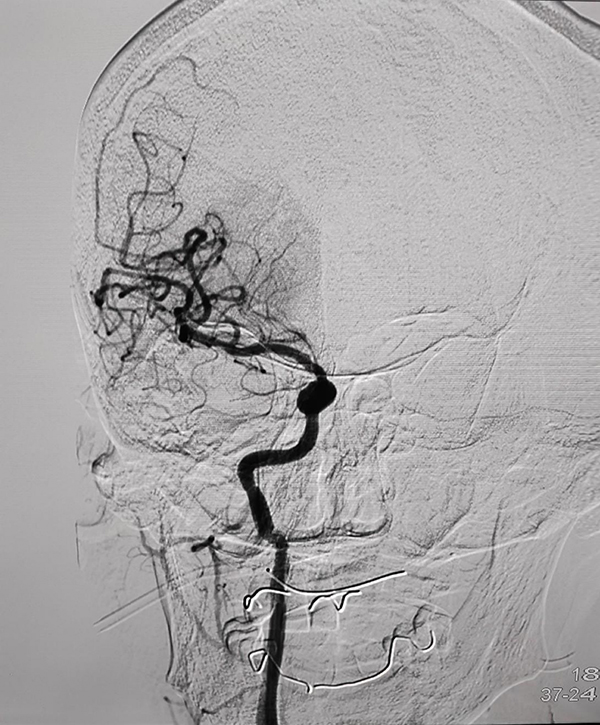

CTP检查结果提示,姬阿姨颅内核心梗死体积约9.6ml(红色区域),但低灌注区域体积高达81ml(绿色区域)(图2),低灌注区域越大,代表可挽救的脑神经细胞越多,手术开通的价值越大,可见患者颅内低灌注区域远远大于核心梗死区域,颅内动脉取栓术手术指征进一步明确。在与患者家属积极沟通,征得家属同意后,王建峰主任团队在国家级高级卒中中心李健主任的指导下,急诊进行了全脑血管造影术+颅内动脉取栓术,术中证实右侧大脑中动脉起始段闭塞(图3),并急诊进行了右侧大脑中动脉取栓术,术中抽拉出一块暗红色血栓,术后可见右侧大脑中动脉血流通畅(图4)。术后1周,在神经内科一病区医护人员的精心照料下,姬阿姨完全康复,说话言语清晰,对答切题流畅,四肢肌力活动恢复正常,现已康复出院。

图3